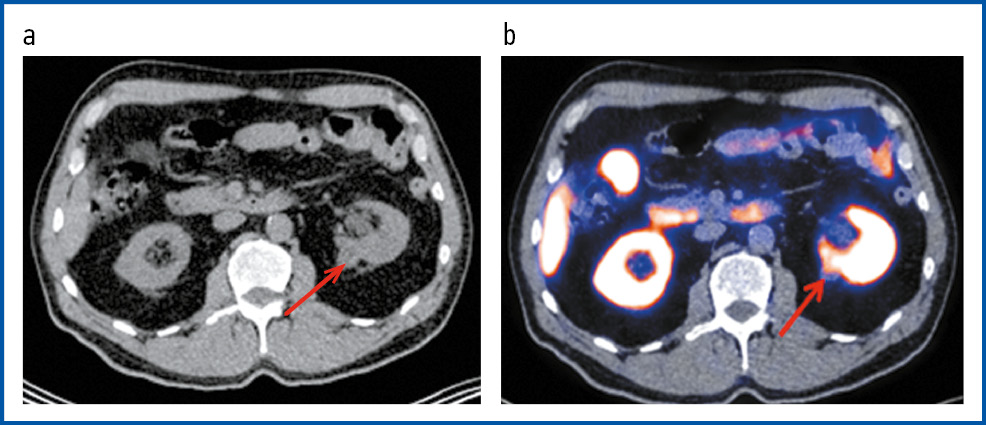

Рис. 2. Пациент С., 74 года. ПЭТ/КТ с 18F-PSMA. В аксиальной проекции КТ (a) и ПЭТ/КТ-исследовании (b) левая почка уменьшена в размерах. В ее верхнем сегменте визуализируется кистозно-солидное образование с гиперфиксацией РФП, SUVmax 12,8, размерами 26 × 23 мм. Чашечно-лоханочные системы и мочеточники не расширены. Конкрементов не выявлено.

Fig. 2. Patient S., 74 years old. PET/CT with 18F-PSMA. In the axial view of CT and PET/CT imaging, the left kidney was reduced in size. In its upper segment, a cystic-solid mass was visualized with RPA hyper uptake, SUVmax 12.8, 26 × 23 mm. The renal collecting systems and ureters were not dilated. No concretions were detected.